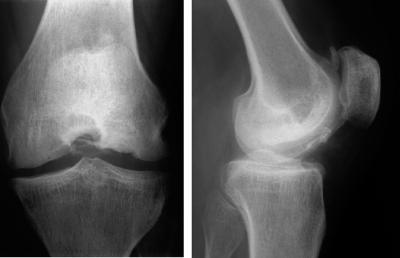

Multiple epiphyseal dysplasia (MED) is a common genetically and clinically heterogeneous skeletal dysplasia characterized by early-onset osteoarthritis, mainly in the hip and knee, and mild-to-moderate short stature. Here we report on a 6-generation MED family with 17 affected members.

We identified an exon 3 donor splice mutation in the COL9A2 gene in all affected family members. Clinical, radiographic, and questionnaire data from affected family members suggested that MED caused by COL9A2 mutations starts in early childhood with knee pain accompanied by delayed ossification of femoral epiphyses. The disease then either stabilizes during puberty or progresses with additional joints becoming affected; joint surgery might be necessary. The progression of the disease also affects muscles, with increasing atrophy, resulting in muscle fatigue and pain. Muscular atrophy has not been reported earlier in cases with COL9A2 mutations.

我们在所有受累的家族成员中均发现 COL9A2 基因外显子 3 供体位点剪接突变。受累家族成员的临床、影像学和问卷数据表明,COL9A2 基因突变引起的 MED 从儿童早期开始出现膝关节疼痛,伴股骨骨骺骨化延迟。然后,疾病在青春期稳定,或随更多关节受累而进展;可能需要关节手术。疾病的进展也会影响肌肉,导致肌肉萎缩,引起肌肉疲劳和疼痛。肌肉萎缩在 COL9A2 突变病例中尚未有报道。